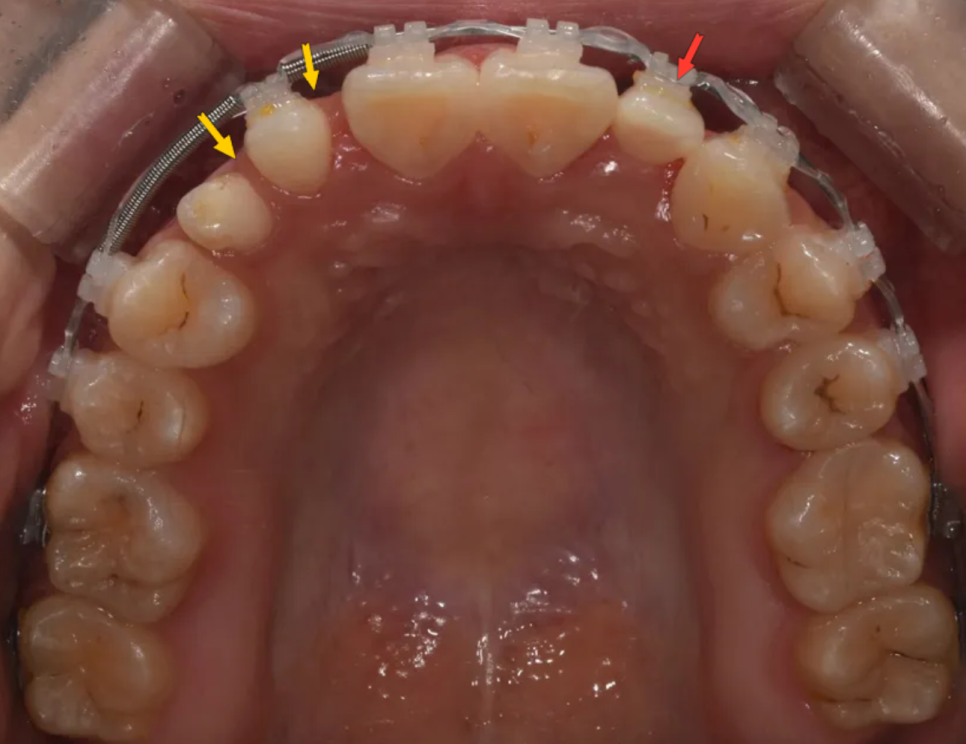

2022년 12월부터 교정치료를 시작했습니다. 이때 교정의 목표는 단순히 치아를 가지런히 배열하는 것이 아니었습니다. 향후 심미보철을 성공적으로 진행하기 위한 최적의 공간을 확보하는 것이 핵심 목표였습니다.

구체적으로는 다음과 같은 작업들이 이루어졌습니다:

오른쪽 위 측절치(왜소치)와 잔존유치 주변에 보철물이 들어갈 수 있는 적절한 공간을 확보

왼쪽 위 측절치 결손 부위에는 교정 중 치아 모양의 임시 장치를 붙여 심미성을 유지

왼쪽 위 첫째 작은어금니의 회전을 개선

전체적인 치아 배열 정리

이 환자분에게 있어 교정치료는 단순한 배열 정리가 아니라, 보철 성공을 위한 중요한 사전 작업이라는 점을 꼭 기억해주세요. 교정과 보철이 유기적으로 연계되어야 최종적으로 좋은 결과를 얻을 수 있습니다.

교정 종료 – 보철을 위한 공간(노랑색)이 확보되고, 결손 부위에 임시 치아(붉은색)가 부착된 상태